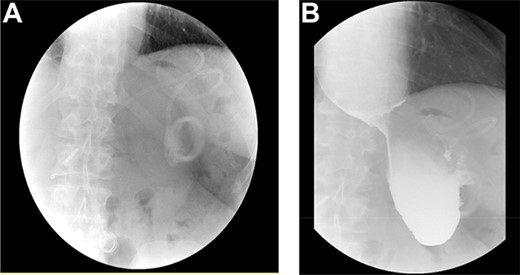

As part of the assessment, computed tomography (CT) coronary angiogram study was performed and it demonstrated a large fluid-filled oesophagus causing partial compression of the left atrium. Barium swallow (Fig. 1A and B), CT chest and abdomen (Fig. 2A and B) and transthoracic echocardiography (TTE) showed a 7.1-cm dilated oesophagus causing left atrial compression and a small hiatal hernia (Fig. 3).

(A) CT coronal image of chest and abdomen demonstrating megaoesophagus secondary to the LAGB; (B) CT axial image of chest demonstrating megaoesophagus causing left atrial compression.